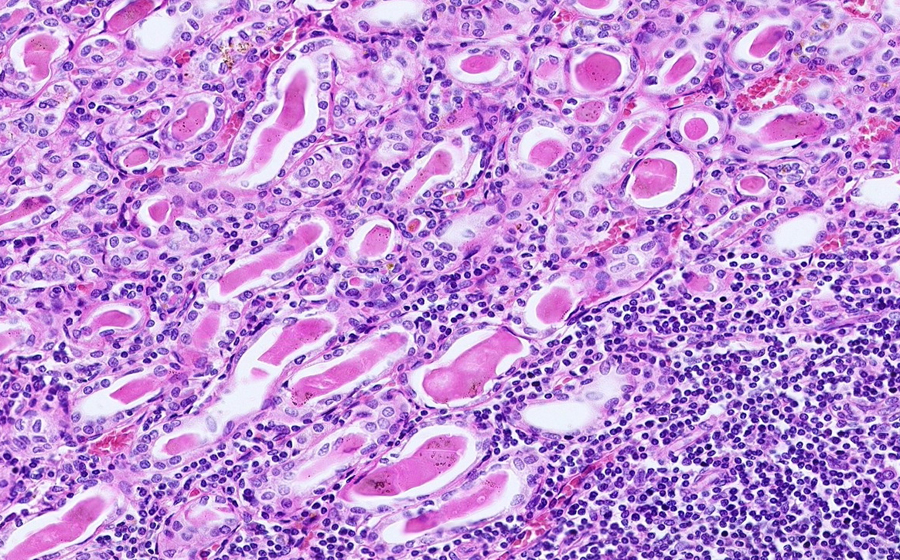

Slide 3: Glomerulonephritis - chronic

Histologic section of kidney from a patient with chronic glomerulonephritis. (click here to review normal tissue)

Image 5 - 200X

Slide 3 - Image 5